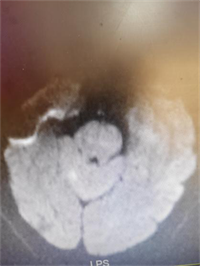

急诊科医师接诊时患者已中度昏迷,鼾式呼吸,小便失禁。立即完善急诊头颅CT提示左侧丘脑及侧脑室旁脑软化灶。头颅MRI提示小脑、两侧枕叶、左侧顶叶急性脑梗死。